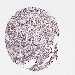

UROTHELIAL CANCER - Protein expressioni

A mouse-over function shows sample information and annotation data. Click on an image to view it in a full screen mode. Samples can be filtered based on level of antibody staining by selecting one or several of the following categories: high, medium, low and not detected. The assay and annotation is described here.

Note that samples used for immunohistochemistry by the Human Protein Atlas do not correspond to samples in the TCGA dataset.

Antibody stainingi

Antibody staining in the annotated cell types in the current human tissue is reported as not detected, low, medium, or high, based on conventional immunohistochemistry profiling in selected tissues. This score is based on the combination of the staining intensity and fraction of stained cells.

Each image is clickable and will lead to virtual microscopy that enables deeper exploration of all samples and also displays staining intensity scores, fraction scores and subcellular localization as well as patient and tissue information for each sample.

Antibody HPA038450

Antibody HPA038451

Staining

High

Medium

Low

Not detected

Intensity

Strong

Moderate

Weak

Negative

Quantity

>75%

75%-25%

<25%

None

Location

Nuclear

Cytoplasmic/membranous

Cytoplasmic/membranous,nuclear

Urothelial carcinoma, High grade

Urothelial carcinoma, Low grade

Urothelial carcinoma, NOS